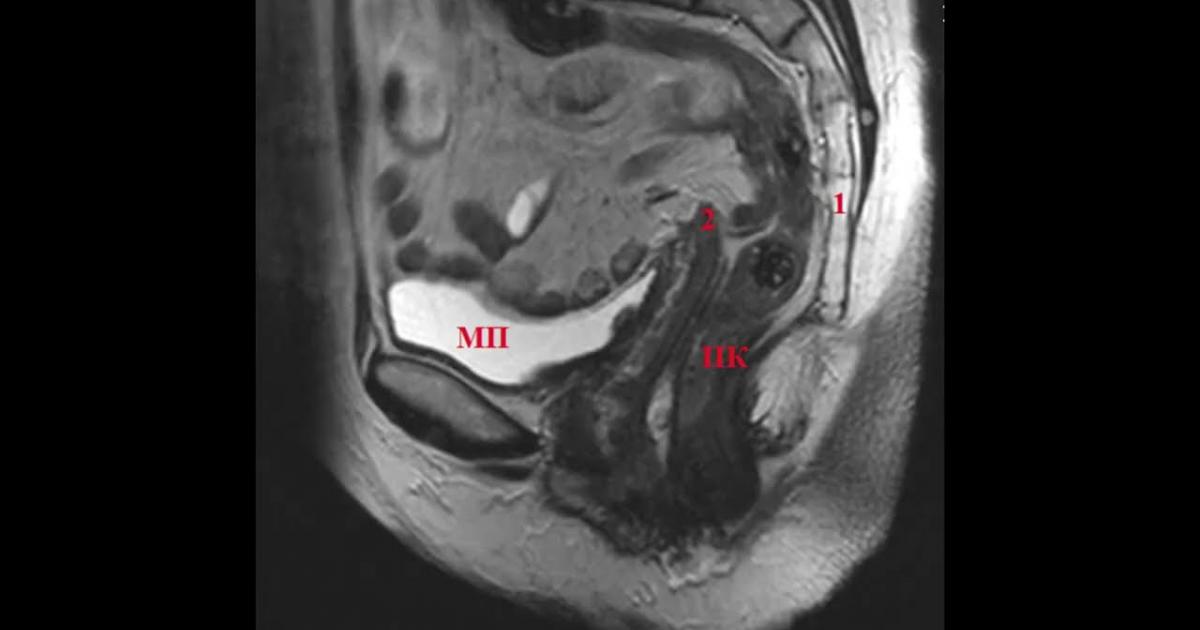

МРТ саркомы шейки матки: диагностика и лечение